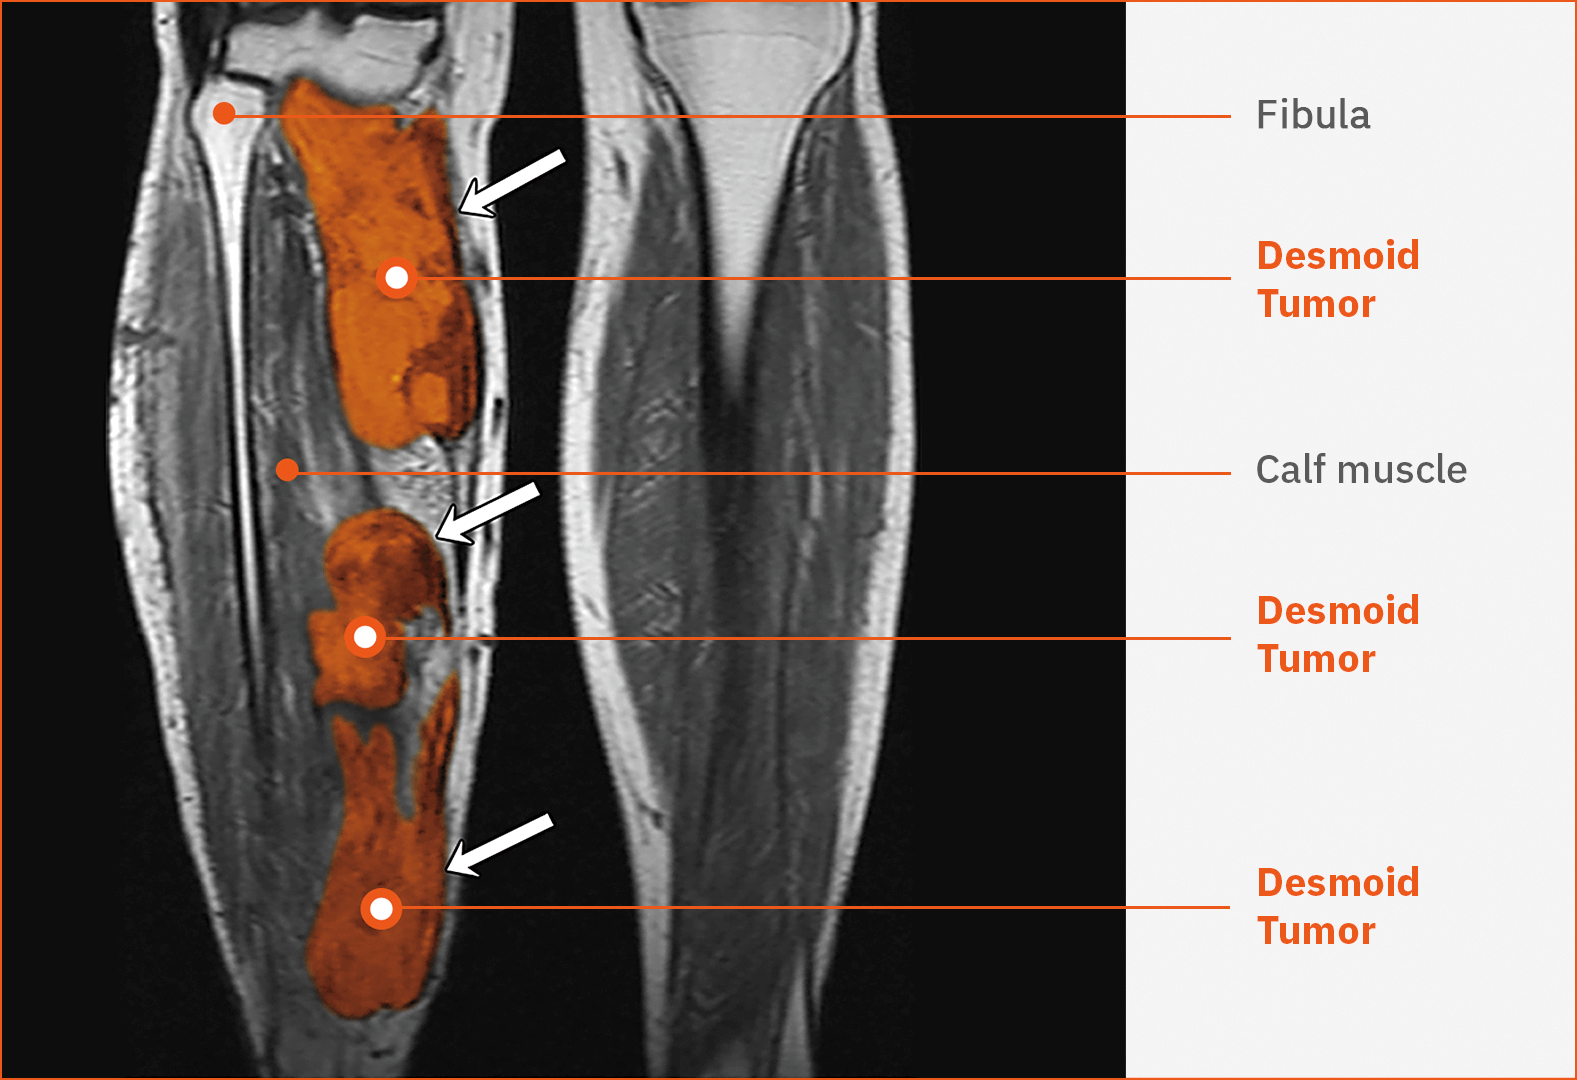

Lower Extremities

16%

Multifocal desmoid tumors in the leg40

This T1-weighted MRI shows multiple, unresectable, sporadic desmoid tumors (white arrows) in the right leg of a female patient aged 40 years. The heterogeneous masses are infiltrating the calf region posteromedially.